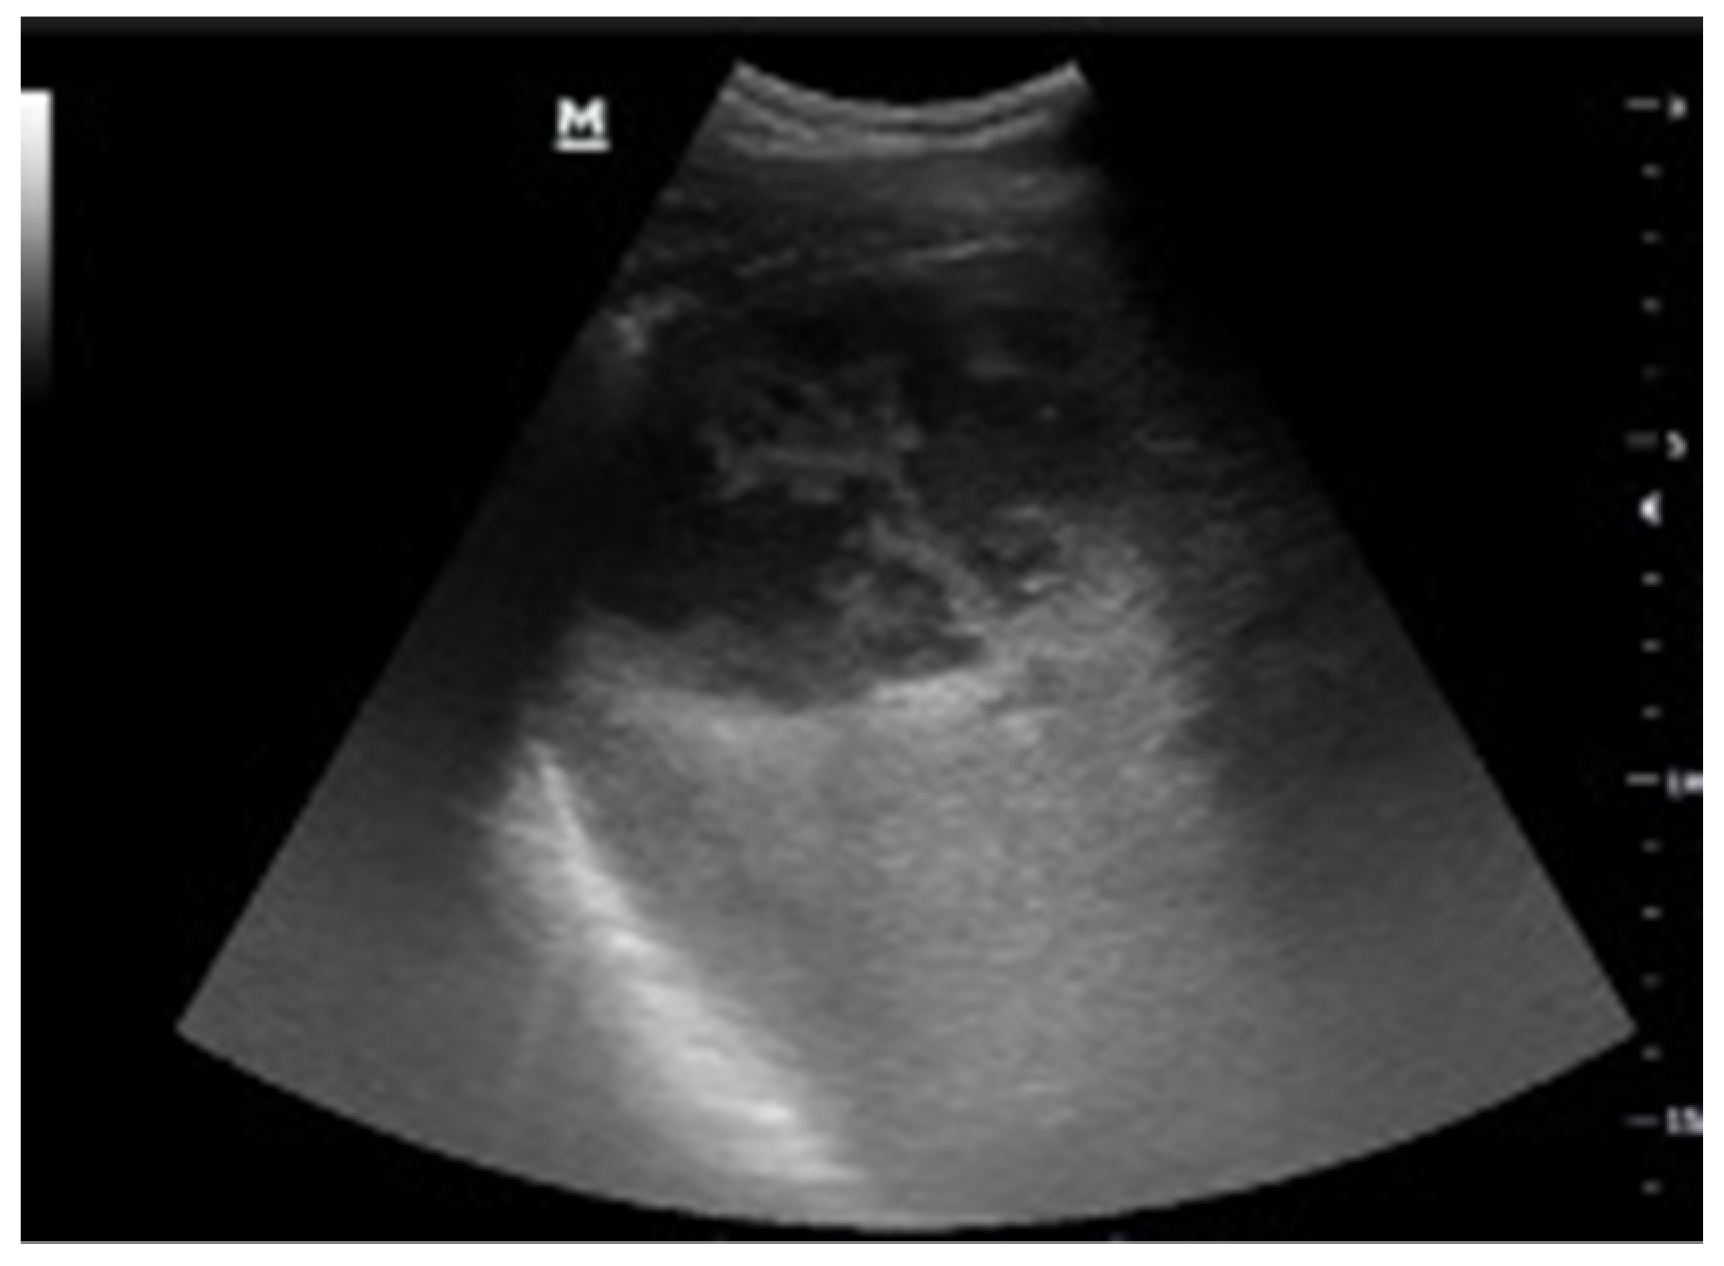

Intraparenchymal Fluid Lesions

| Intraparenchymal | Infected cyst Infectious cyst Hematoma Abscess Aneurysm Pseudoaneurysm |